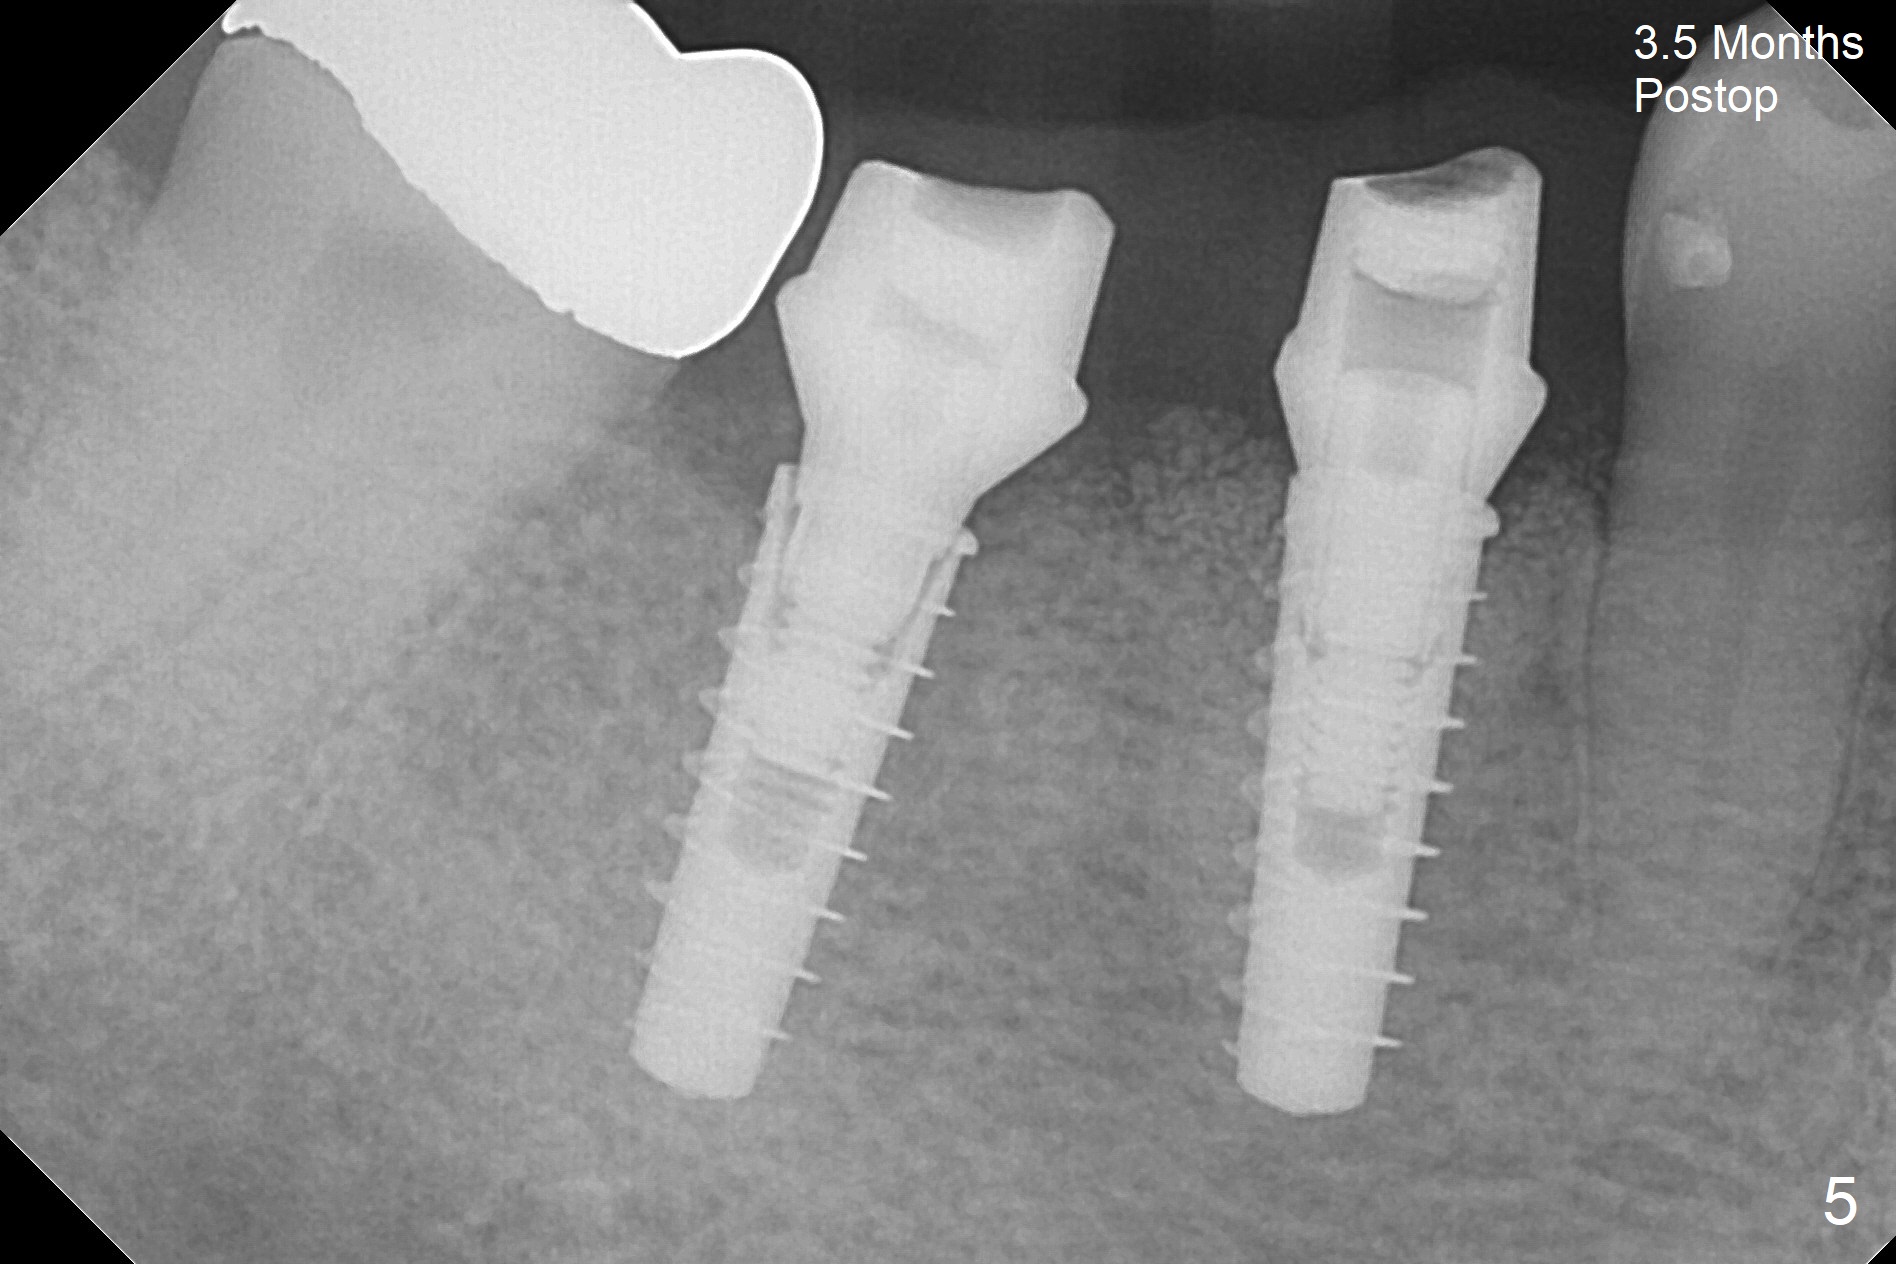

After incision, the ridge at #29 and 30 is found ~ 5 mm wide buccolingually. To place a 4x11 mm IBS implant at #30, the ridge is expanded using BEB technique (bone expansion and bending, Fig.1). It appears that the initial osteotomy at #29 is mesial (Fig.1 yellow dashed line: the distal surface of the root of the tooth #28). After moving the osteotomy distal, the final implant position at #29 (4x11 mm) is within normal limit (Fig.2). The bone at #29 seems to be not so dense that bending (using 1.6 mm drill) is not necessary (using Magic Split and Magic Expanders 3 and 3.8 mm). Later the implant at #30 (4x11 mm) is placed deeper (Fig.3). After placing bone graft around the implants/abutments and suturing, the ridge looks wider with apparent formation of the gingival bands around the abutments (Fig.4 *). Three months and a half postop, bone loss is minimal (Fig.5) and gingival bands forms around the abutments (Fig.6). Fig.7 is taken 1 month post cementation (panoramic X-ray). The patient chews normally 1 year (Fig.8) and nearly 2 years (Fig.9,10) post cementation. The crown at #31 needs recementation 2 years 7 months post #30 cementation; the incomplete seating of the abutment was noted for the first time (Fig.11). Five months later the patient is going to be retired and wants to travel abroad. After approval, the access hole was reopened; articulating paper shows under occlusion of the crown (Fig.12). Since the gap between the abutment and the implant is large, the abutment/crown complex seems to be necessary to be turned (Fig.13 curved arrow). The proximal surfaces of the crown need to be trimmed (straight lines). After turning, the crown sits down with screw tightening; the patient feels pain from the gingival cuff (Fig.14). After turning, the abutment appears to be completely seated (Fig.15). In fact the mesial and distal surfaces of the crown should have clearance from the neighboring teeth (Fig.14) so that pick-up impression is able to hold the crown/abutment complex securely (Fig.16: *). The crown is separated from the abutment after crown repair. They are seated together (loose connection) using the crown as a guide to seat the abutment. BW is taken without the crown. It appears that the abutment remains seated completely (Fig.17). The apical space is equal between #29 and 30 (Fig.17, as compared to Fig.5).